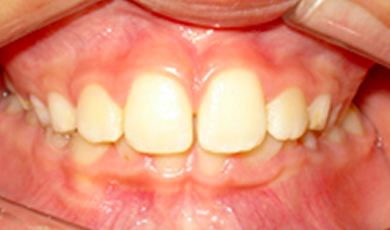

Canino inferior esquerdo incluso (dente 33)

As imagens abaixo retratam um caso clínico em que a paciente compareceu ao consultório para avaliação ortodôntica e por meio da imagem radiográfica (panorâmica) foi possível identificar que o canino inferior esquerdo (dente 33) encontrava-se incluso, sendo necessária a intervenção ortodôntica para o seu tracionamento.